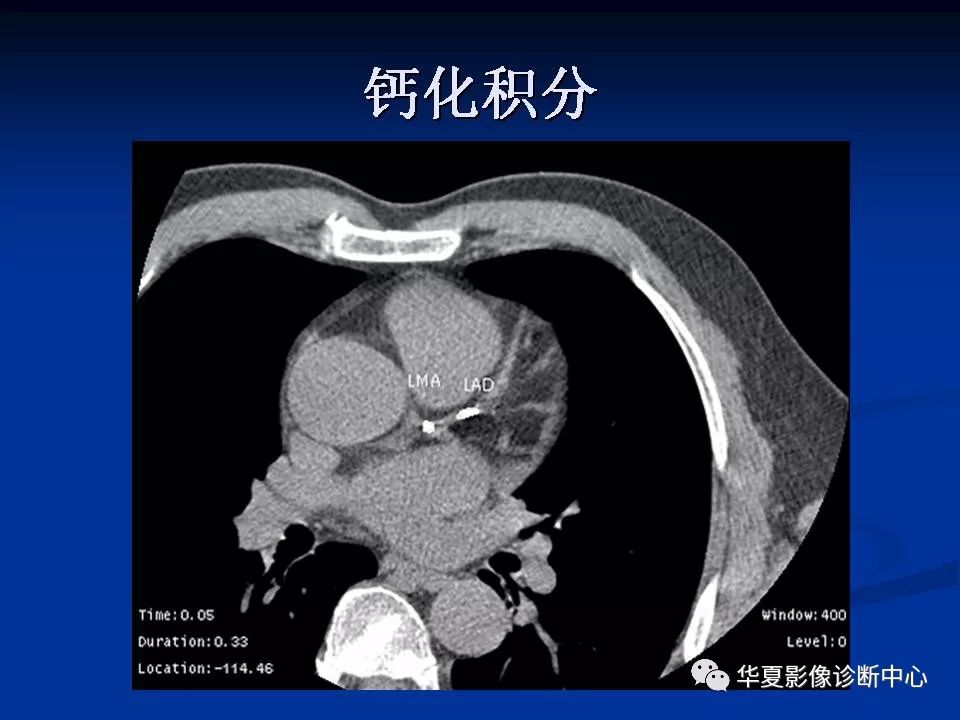

详细解读冠状动脉及冠心病ct

图片尺寸960x720